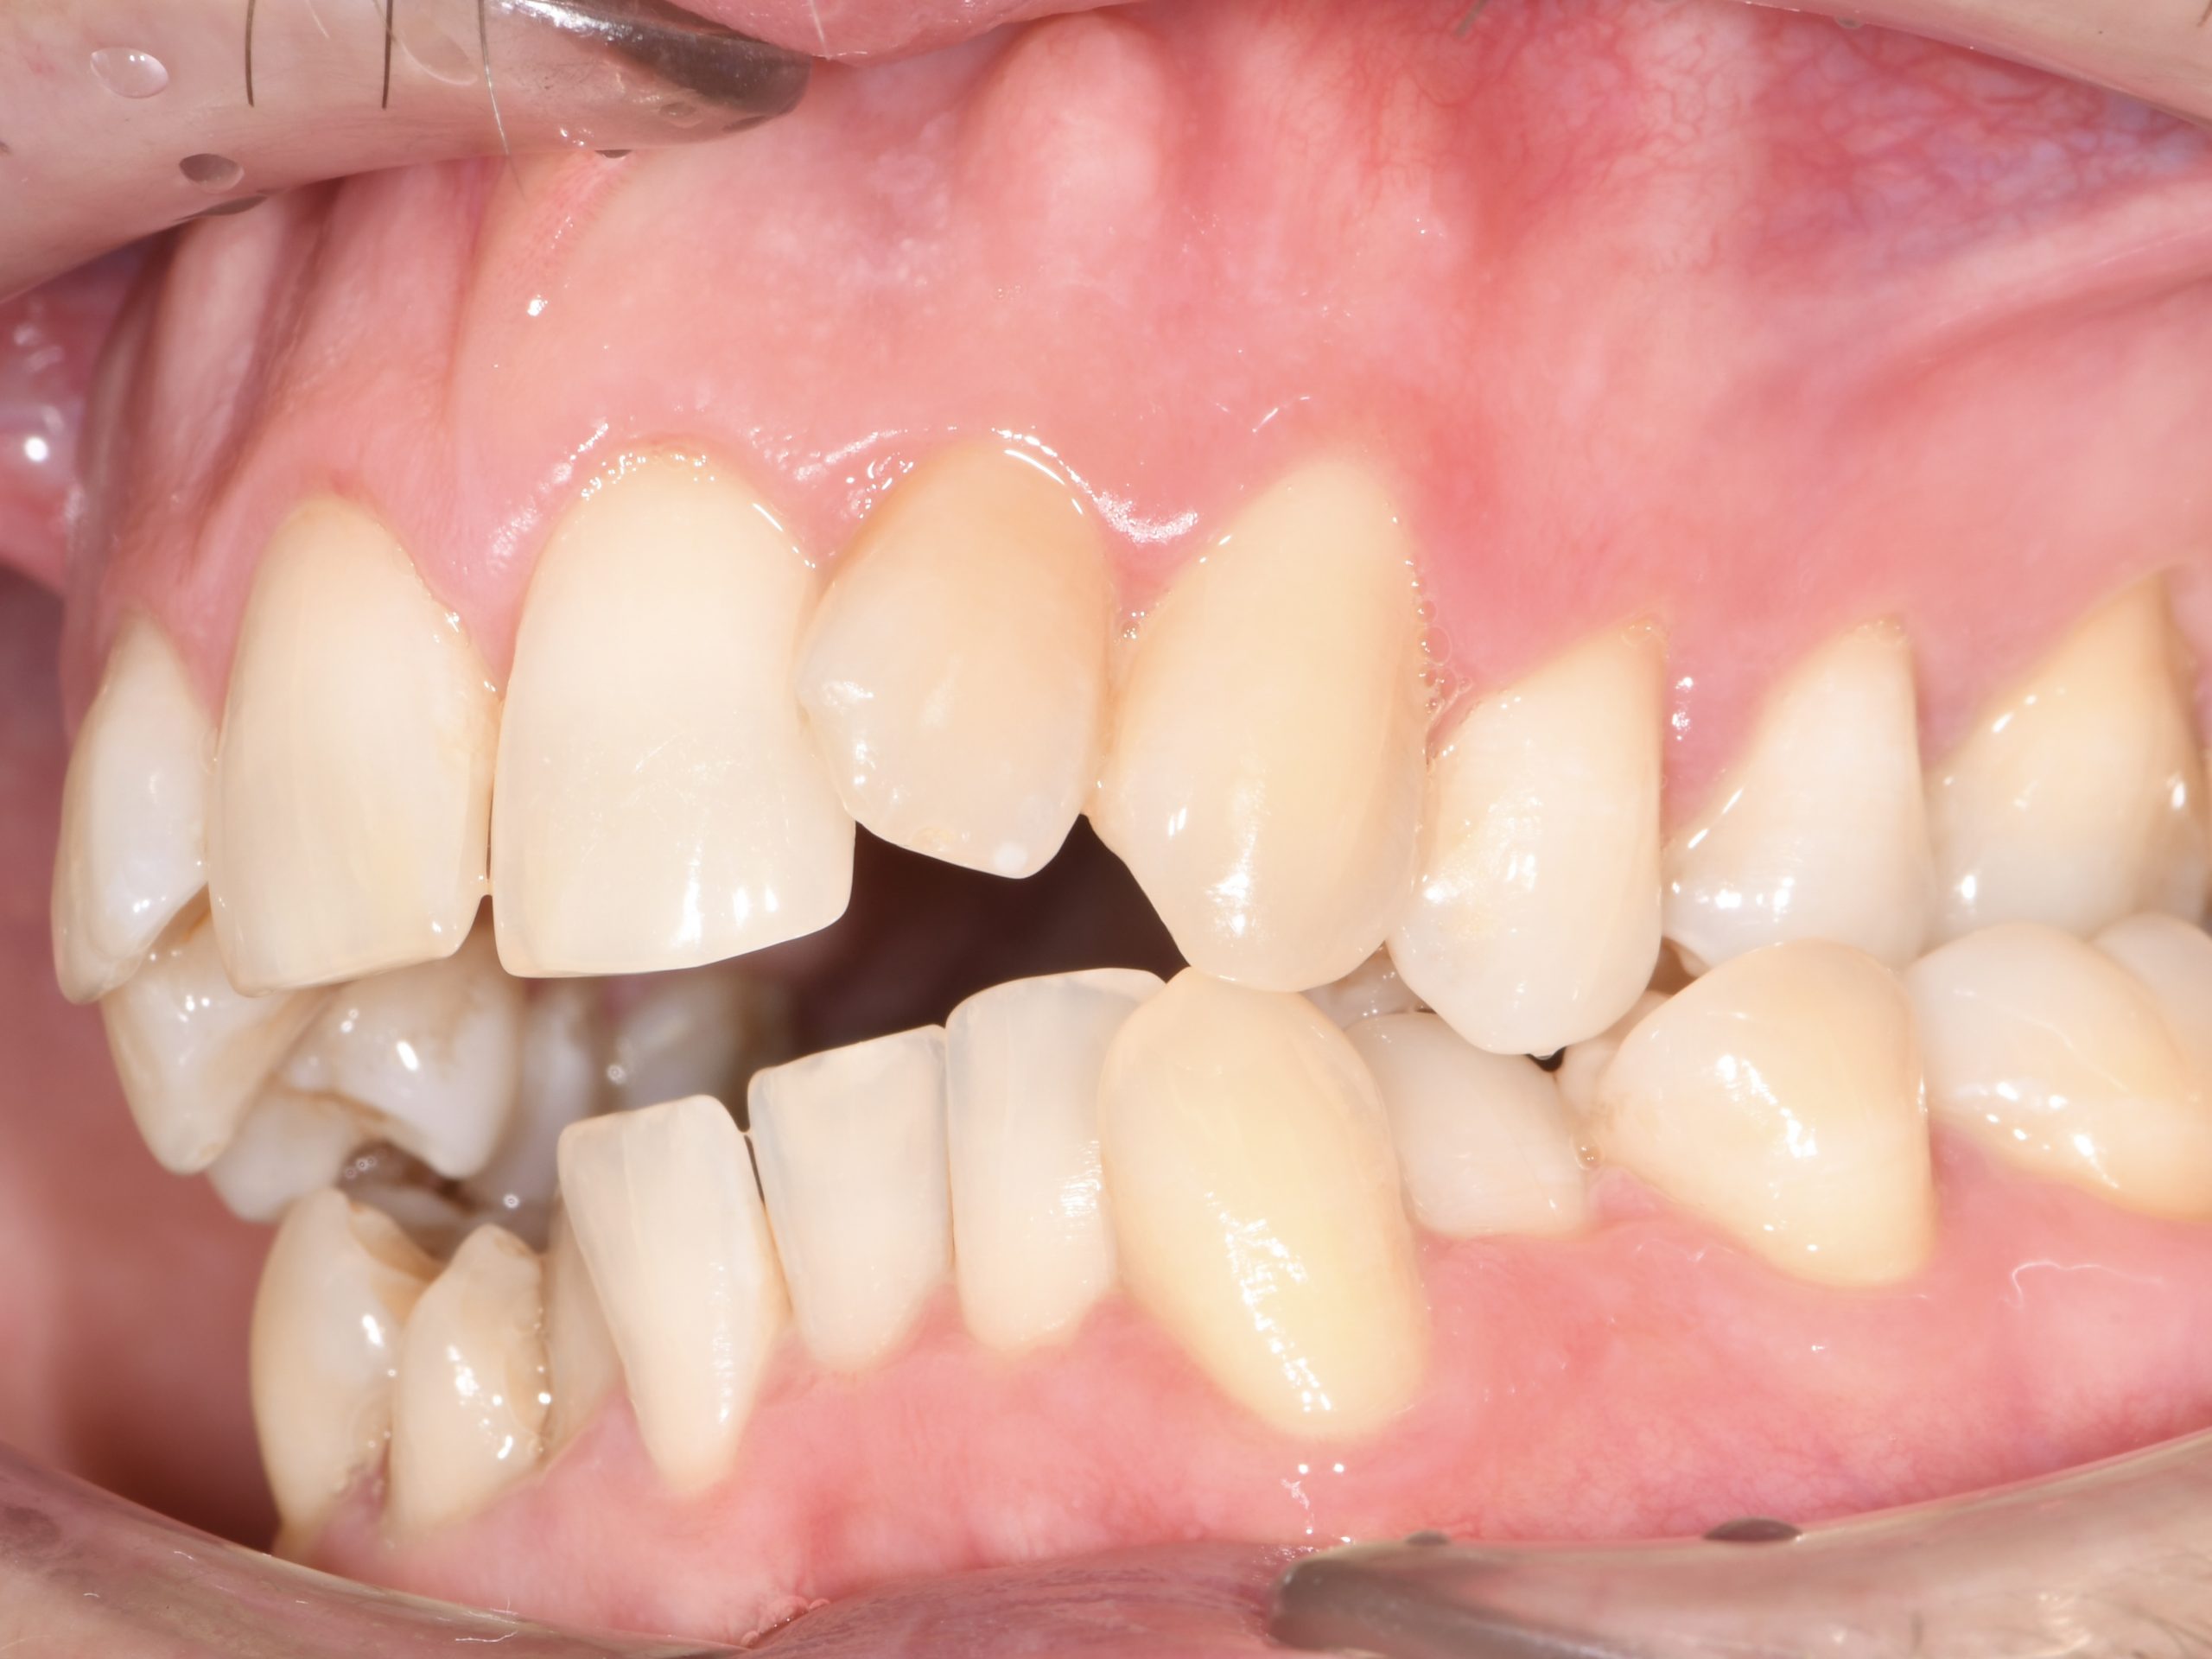

Az elmúlt évekből rengeteg szakmai referenciát tudnánk bemutatni, amelyek különböző fogszabályozási problémákat oldottak meg. Válogatva a több száz esetből, ezen az oldalon olyan képeket, információkat igyekeztünk bemutatni, amelyeknek a segítségével a jövőbeni pácienseinknek azt tudjuk üzenni: A Te fogsorod is lehet gyönyörű!